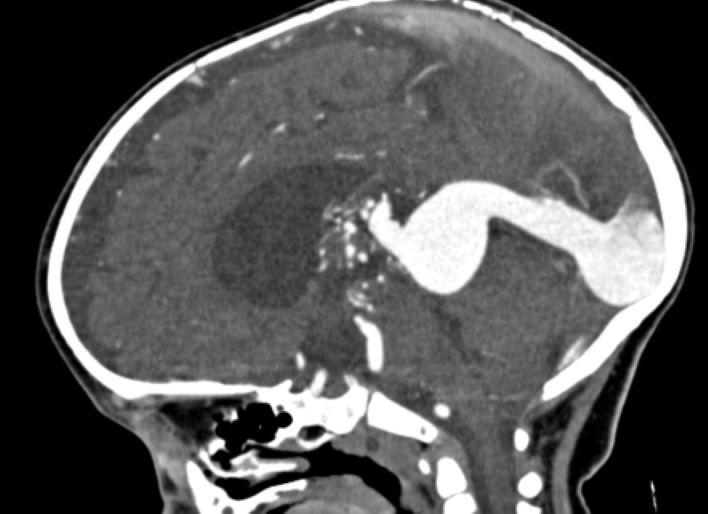

vogm

Vein of Galen malformation

Game-Changing In Utero Brain Surgery

In March, doctors in Boston performed the world's first repair of a rare brain condition—known as vein of Galen malformation—to an unborn child. The successful procedure was performed while the baby was still in utero, giving the child a greatly improved chance of leading a healthier life. Before this, treatment of this brain malformation after birth could lead to permanent damage or even prove fatal.